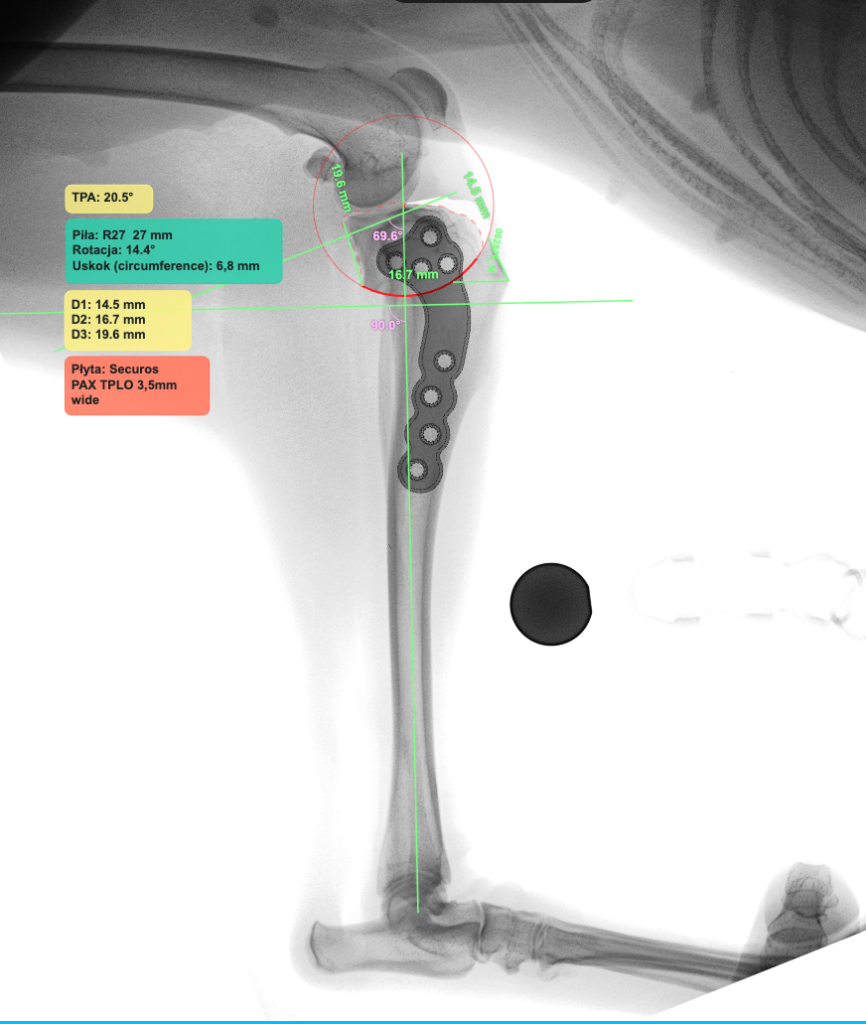

Standardem naszej Kliniki jest planowanie zabiegu z wykorzystaniem oprogramowania vPOP Pro. Pozwala ono na pomiary kątów stawu kolanowego i dopasowanie odpowiedniego rozmiaru piły, którą wykorzystujemy do cięcia kości piszczelowej, dobrania odpowiedniego rodzaju i rozmiaru implantu (płyty), rozmiaru śrub.

Płyty Securos PAX, Arthrex TPLO System, iWET TPLO System są implantami, które na codzień używane są w naszej Klinice